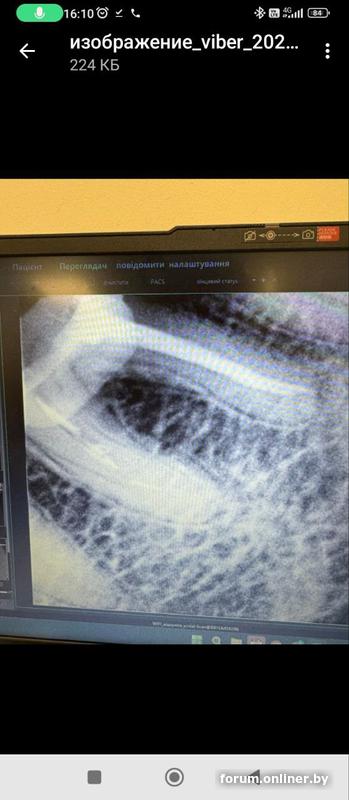

Вот это фото из клиники, которое прислали по запросу, не ясно какое до перепломбировки, какое после. Вот так и выслали, как фото с компьютера. Может будет полезно. Но первое с потемнением более свежее, а это старше где то сразу после лечения или в процессе или до, врач не уточнил и дат на фото нет.